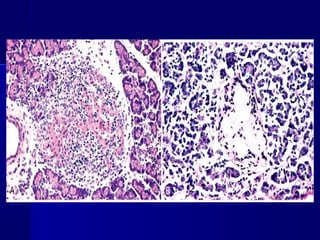

Insulitis en Diabetes Mellitus tipo 1

Insulitis en DiabetesMellitus tipo 1

 PÁNCREAS:PÁNCREAS: reducción de su tamaño y del númerodreducción de su tamaño y del númerod

e islotes. También sustitución de los islotes pore islotes. También sustitución de los islotes por

amiloide e infiltarciones leucocitarias (insulitis) en DMamiloide e infiltarciones leucocitarias (insulitis) en DM

tipo I que empiezan a presentar síntomas.tipo I que empiezan a presentar síntomas.